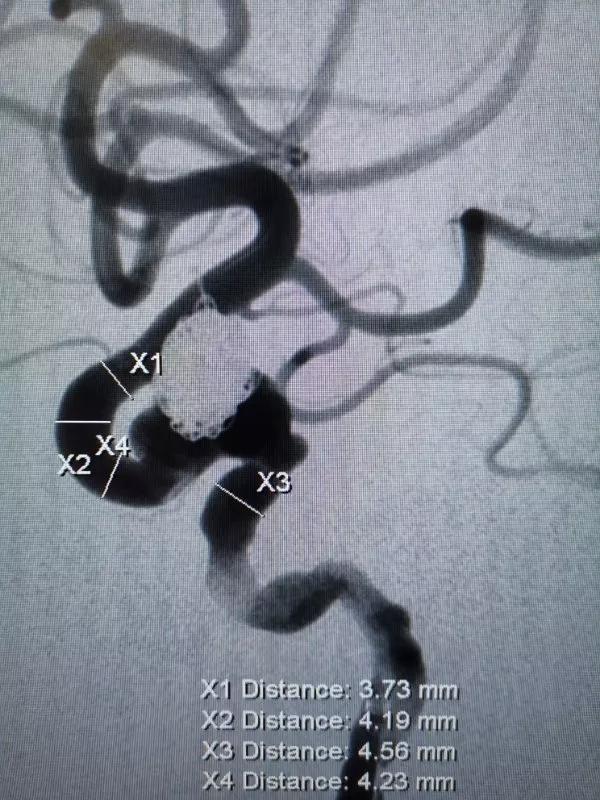

再行右侧颈内动脉血流导向装置置入术:将8F Envoy导引导管置入右侧颈总动脉,105cm 6F Navien导引导管头端置入颈内动脉岩骨段,造影见海绵窦段3个动脉瘤,由近及远直径一次为5mm、8mm、9mm,颈内动脉床突上段可见一大小约为5×4mm的宽颈动脉瘤。

3D重建图像

DSA图像